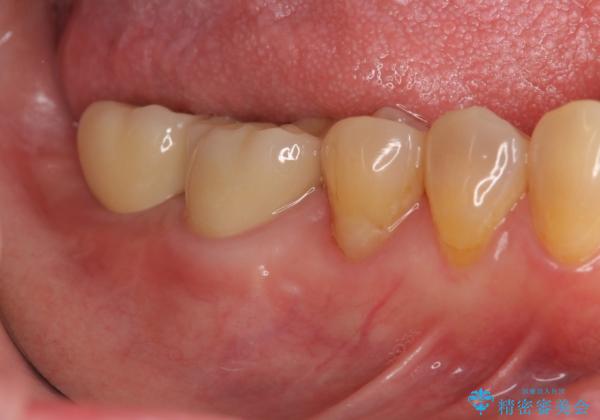

奥歯 インプラントによる機能回復

- 歯を欠損し、噛めないことの治療を希望され来院されました。

インプラントを用いて、しっかりとかめるような治療を計画します。

- 45万円(ストローマンインプラント・骨造成・チタンカスタムアバットメント・ジルコニアクラウン)費用は治療当時の料金となります

最後方臼歯はインプラントを用いることでしっかりと咬合機能を回復することができます。